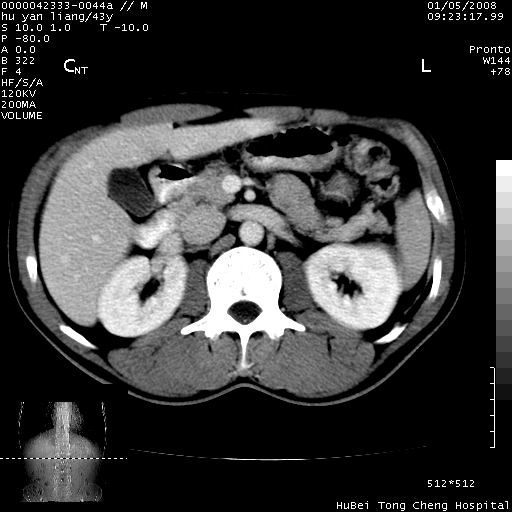

患者 男,43岁。右上腹不适1年余。既往有“肝右叶肝脓肿”病史,经保守治疗后痊愈。

上中腹部ct轴位平扫+增强扫描(层厚10mm,螺距1.0,重建间隔10mm),图像如下:

肝脓肿后遗症,肝右叶钙化。

肝右叶钙化灶,肝脓肿后遗改变!